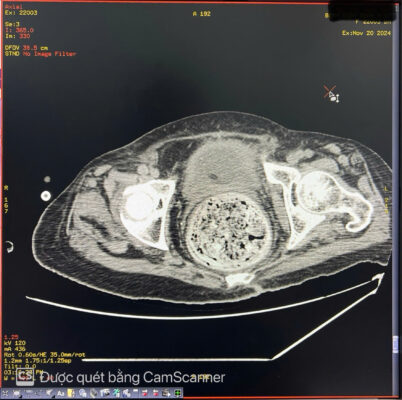

🚑 Một phụ nữ 84 tuổi đến khám với tình trạng đau bụng kèm táo bón mãn tính lâu ngày. Khi khám, bụng căng to, nhiều hơn ở bên trái. Sờ thấy một khối u mơ hồ ở hố chậu trái. Chụp X-quang bụng không chuẩn bị cho thấy giãn đại tràng lên và đại tràng ngang, toàn bộ đại tràng xuống chứa đầy phân. Các quai ruột non bị di lệch sang bên phải bụng. Siêu âm bụng thấy bụng căng nhiều hơi. Chụp cắt lớp vi tính (CT) ổ bụng cho thấy đại tràng xuống và đại tràng sigma giãn lớn chứa đầy phân kèm vôi hóa không đều tạo thành một khối u phân trong lòng đại tràng, có kích thước # 8 x9 x 26cm. Đại tràng lên và đại tràng ngang giãn d# 6.4 cm. Hai thận ứ nước độ I. Thành đại tràng dày nhẹ, còn cấu trúc lớp, thâm nhiễm mỡ nhẹ xung quanh, kèm ít dịch hạ vị. Không thấy khối u hoặc hẹp lòng ruột cản trở ở vùng trực tràng-sigma. Bệnh nhân được điều trị bảo tồn bằng thụt tháo và thuốc nhuận tràng. Hiện tại bệnh nhân ổn định, các triệu chứng cải thiện rõ rệt.

Hình ảnh 1 Hình ảnh 2

👉 Tóm lại: U phân là một dạng tắc nghẽn phân nghiêm trọng. U phân được hình thành do tình trạng ứ đọng phân trong đại tràng kéo dài, theo thời gian, các chất cặn bã này sẽ được sắp xếp lại để tạo thành một khối phân cứng, có hình dạng rõ ràng trong lòng đại tràng. Cũng có thể thấy vôi hóa. Đại tràng sigma và trực tràng là những vị trí thường gặp của u phân. U phân thường gặp ở bệnh Hirschsprung, bệnh Chagas, bệnh nhân nội trú bị chấn thương cột sống, bất thường về hành vi và ở bệnh nhân cao tuổi bị táo bón mãn tính. Các biến chứng của u phân bao gồm tắc ruột, loét đại tràng và thận ứ nước do ảnh hưởng của khối. Các lựa chọn điều trị bao gồm sử dụng thuốc thụt, thuốc nhuận tràng và làm sạch trực tràng để giảm tình trạng tắc nghẽn phân và can thiệp phẫu thuật nếu các phương pháp bảo tồn không hiệu quả.